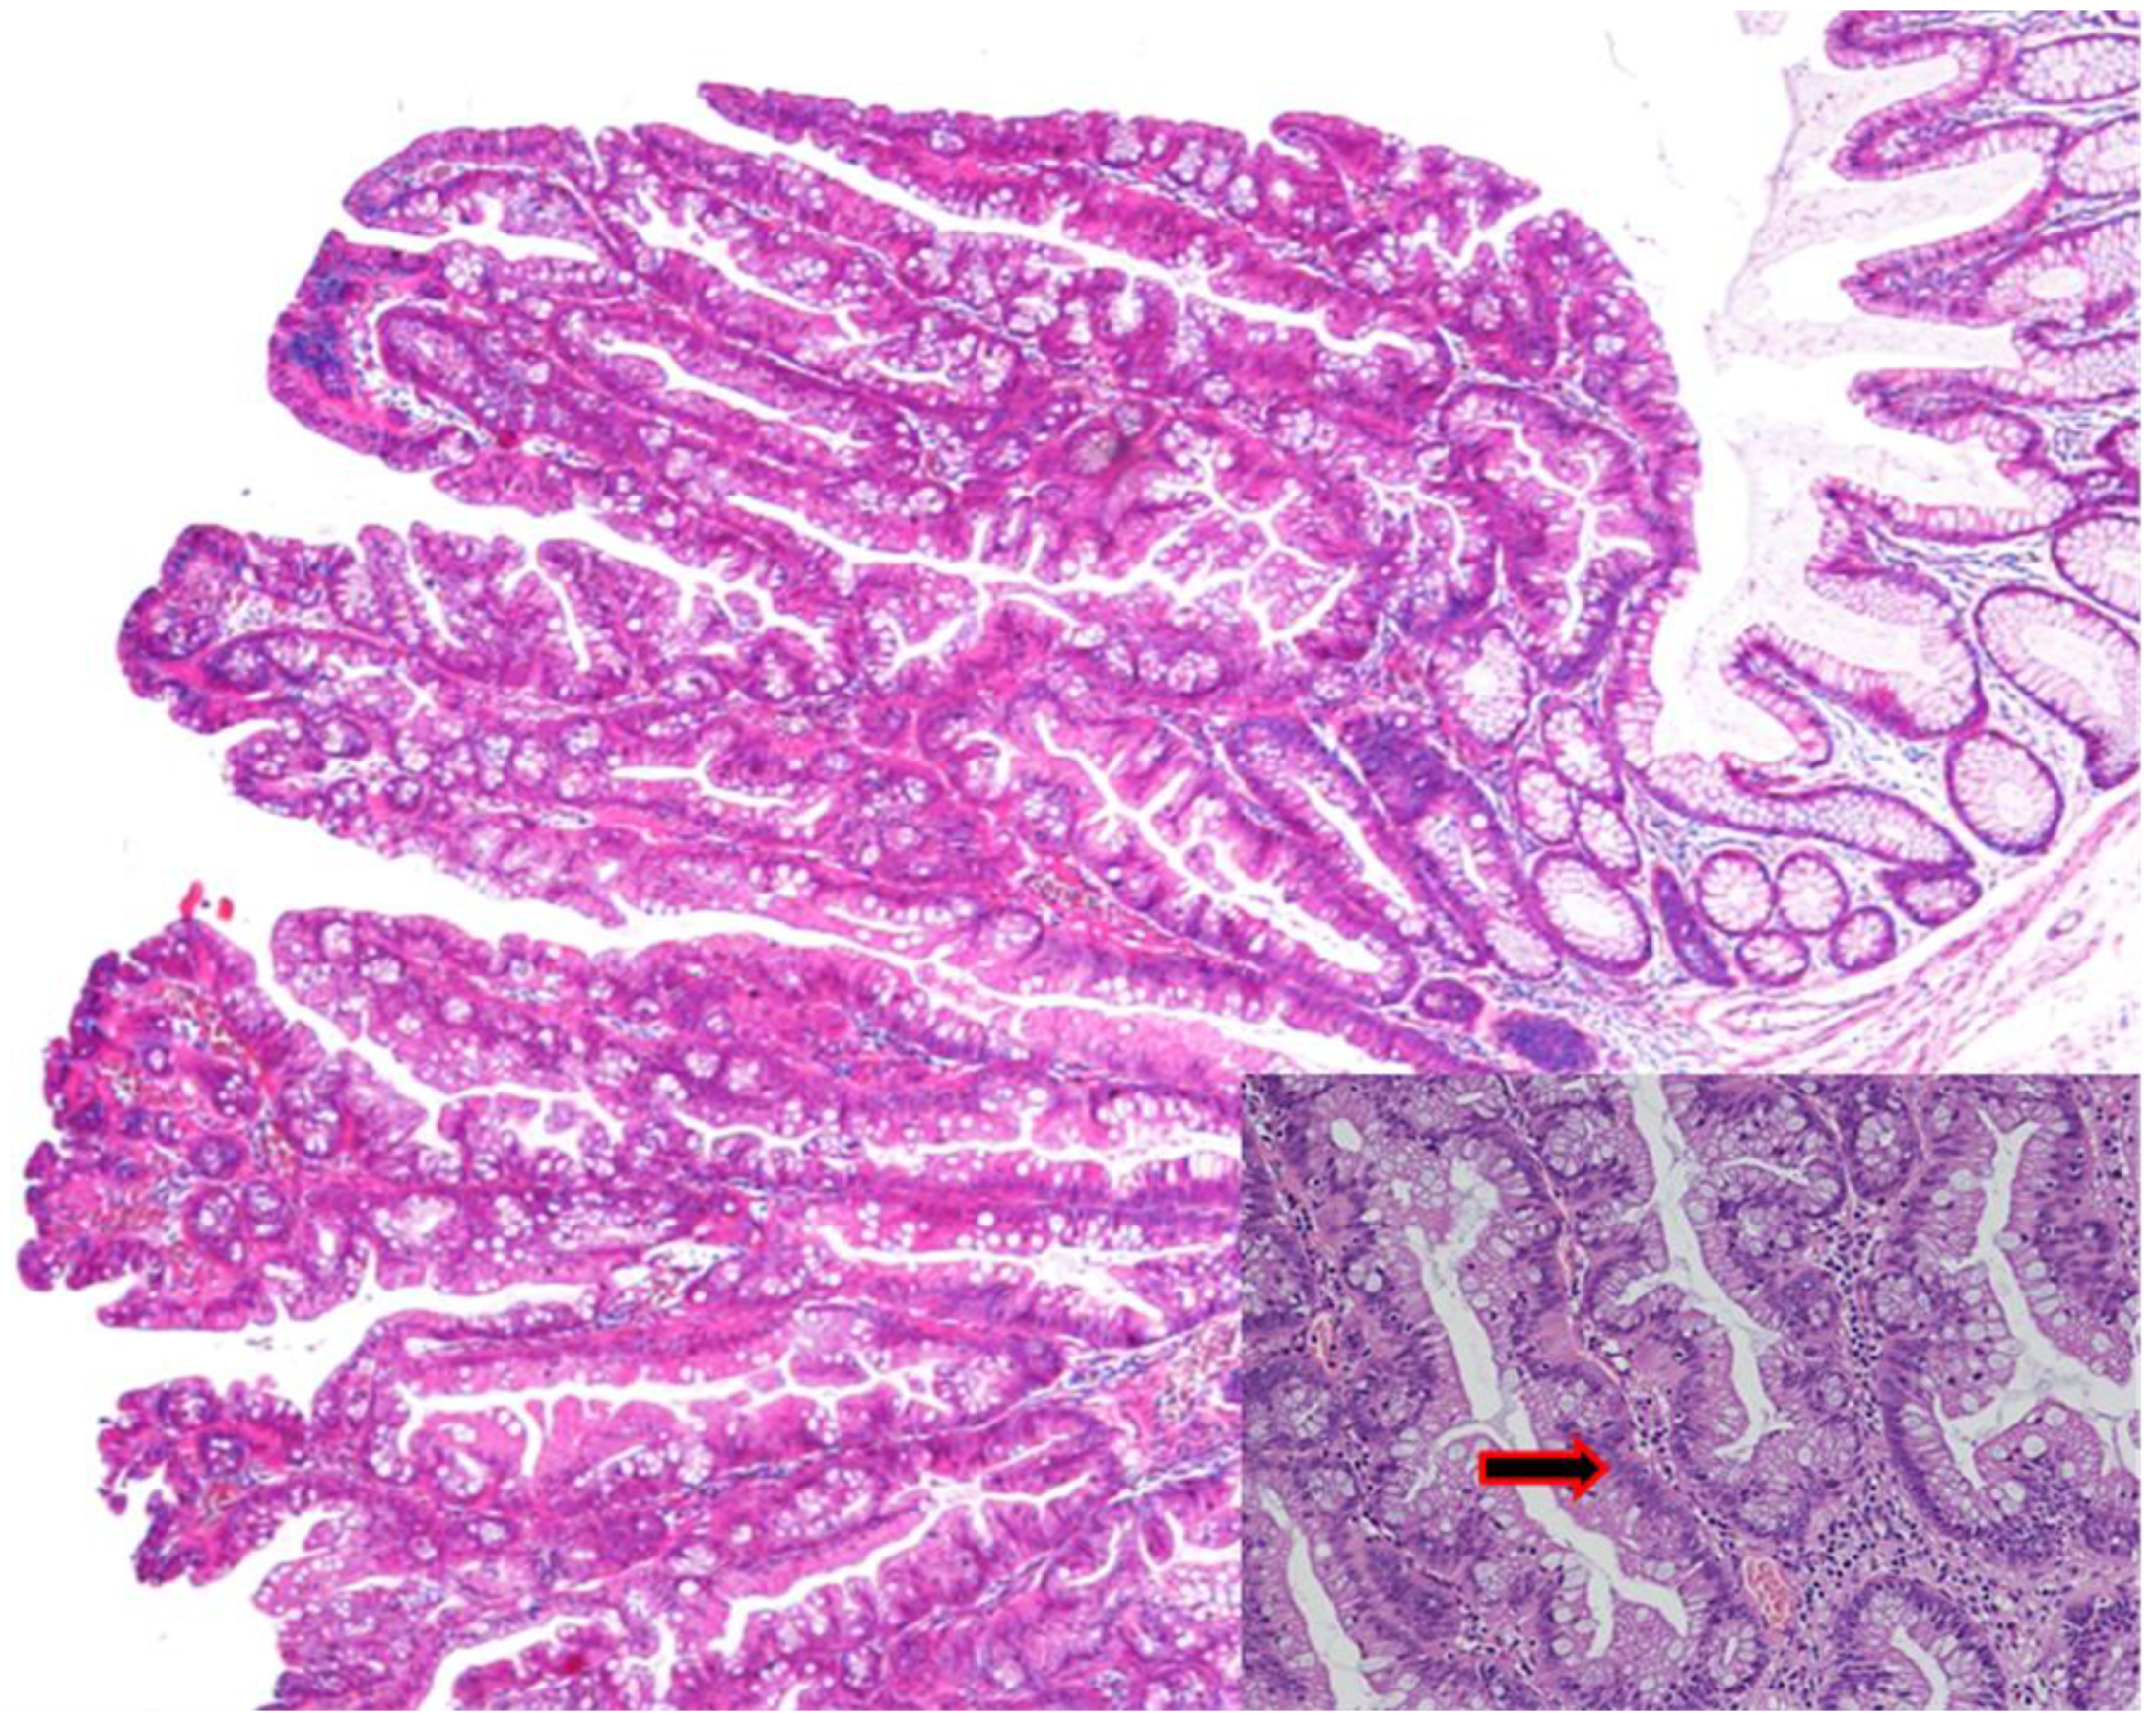

3.2. Sessile Serrated Lesions (SSLs)

Sessile Serrated Lesions with Dysplasia (SSL-Ds)